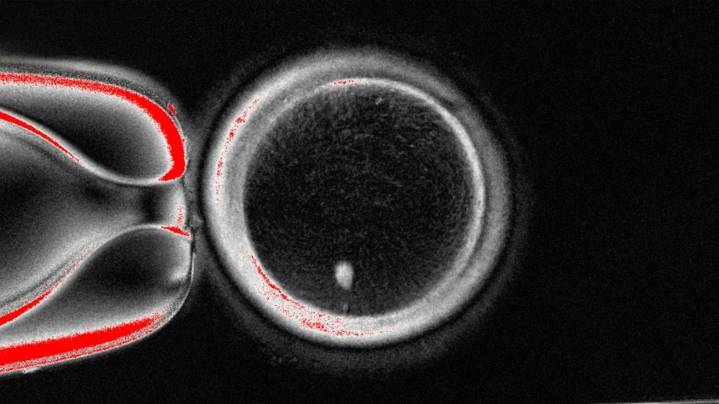

Scientists have turned DNA from human skin cells into "functional" eggs that are capable of producing early human embryos, according to a new study that cautions more research is needed as they're not yet usable.

Why it matters: "In addition to offering hope for millions of people with infertility due to lack of eggs or sperm, this method would allow for the possibility of same-sex couples to have a child genetically related to both partners," said study co-author Paula Amato, professor of obstetrics and gynecology at Oregon Health & Science University, in a statement Tuesday. • This early stage research could one day also be used to treat infertility for women of advanced maternal age "or those who are unable to produce viable eggs due to previous treatment of cancer or other causes,"